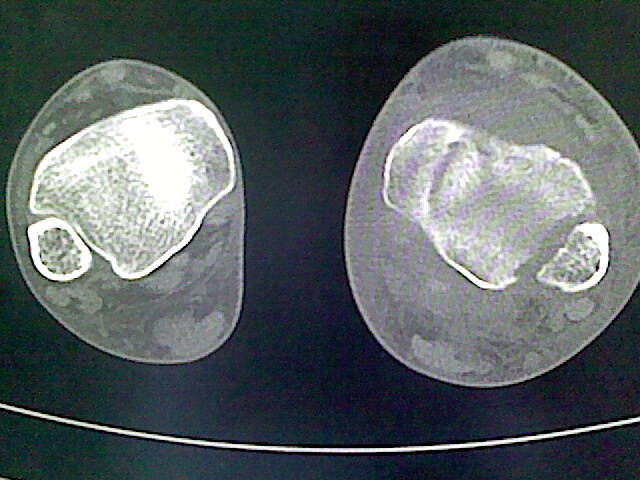

标题: CT16814:男,76岁,左小腿疼痛,不能站立 大家给看看 [打印本页]

男,76岁,左小腿疼痛,不能站立

本例骨质改变主要表现为滑膜或韧带区的骨侵蚀融解(胫腓联合区骨质破坏无硬化边),距骨后部骨质破坏区有硬化边及死骨样改变.所以,本例考虑关节结核可能性大,绒毛膜结节性滑膜炎多发于中年,且极少见于膝髋以外的关节,骨质硬坏也以压陷吸收为主,有明显的硬化边,骨膜增生呈结节状(可以mr鉴别),所以本例暂除外.

另不除外可引起相似表现的其他炎症如布氏杆菌性关节炎等